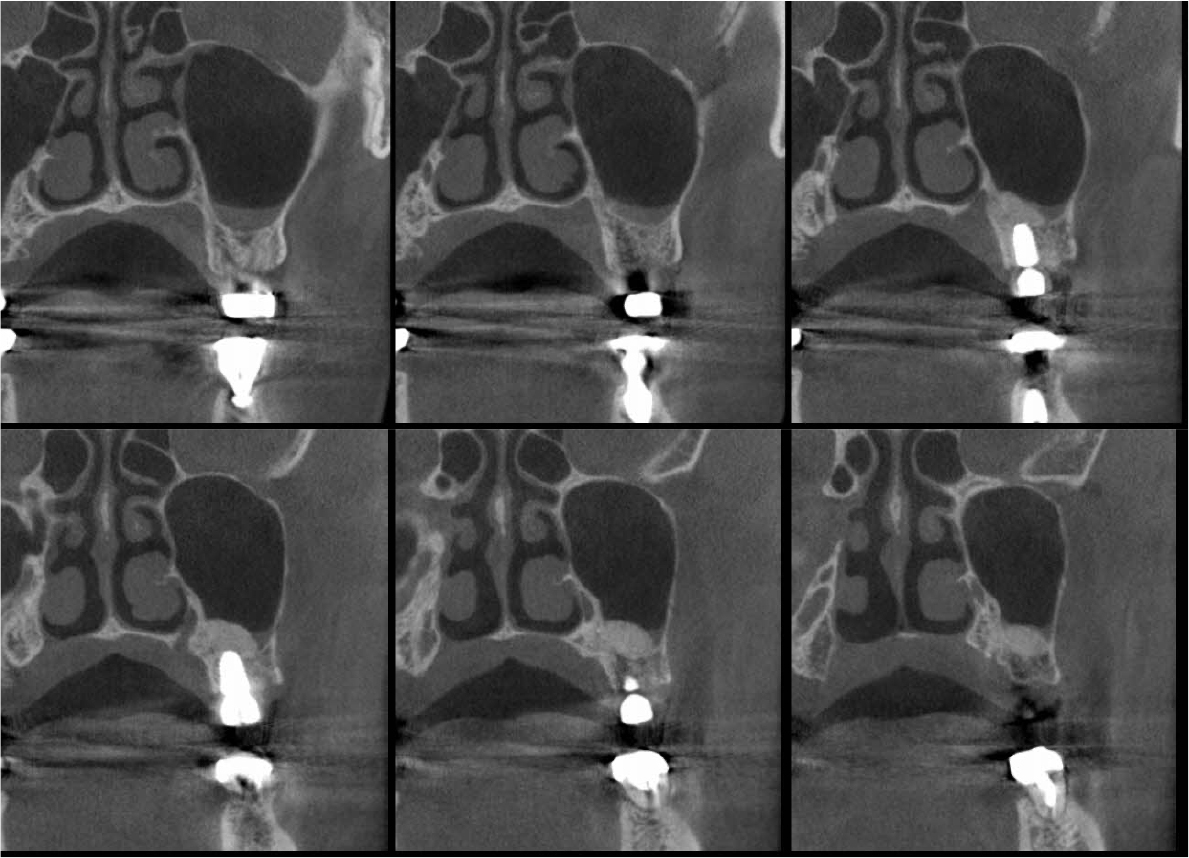

An implant with 5.0 mm diameter and 8.0 mm length (Superline; Dentium, Seoul, Korea) was placed with 0.5 cc of eproteinized bovine bone mineral (DBBM; Bio-Oss®, Geistlich, Wolhusen, Switzerland) by sinus elevation. The implant stability quotient (ISQ) after placement was 64 continually and the healing abutment was placed (6.5 mm diameter, height M size) (Fig. 4A, 4B). Postoperative antibiotics (Sultamox Tab. 500 mg; Alvogen, Seoul, Korea) and analgesics (Somalgen Tab. 370 mg; Alvogen), digestive agent (Beszyme Tab. 470 mg; Dong-A ST, Seoul, Korea) were prescribed for 5 days (30 min after meal). Gargle agent (G.U.M® Dental Rinse S; Sunstar, Osaka, Japan) with no toothbrushing was prescribed to drain and protect the operation area for 2 weeks. Postoperative cone-beam computed tomography (CBCT) showed a dome-shaped elevated membrane with a heterogeneous bone graft surrounding dental implants (Figs. 5 and 6). After 14 days, favorable healing gingiva was confirmed with the stitch-out process (Fig. 7).

Numerous studies have evaluated protocols to increase the success rate of immediate implant placement after extraction. The primary stability of immediate implant placement has been reported to be the most important factor.15 Lioubavina-Hack et al.16 presented at least 3−5 mm residual alveolar bone under the extraction socket as the requirement for successful placement. In this case, a 5 mm residual bone height would be sufficient for primary stability; however, this is not a satisfactory vertical bony height for implant placement. Therefore, the alveolar crestal approach and hydraulic sinus lift technique with DBBM were used for the elevation of the maxillary sinus membrane. As favorable primary stability was guaranteed, the healing abutment was placed consecutively. The sinus membrane was not elevated symmetrically, as ordinary in the case of hydraulic sinus lift, but the fixture was surrounded by sufficient bone graft material verified by CBCT (Fig. 6).

Previous studies have evaluated the positional relationship between the surrounding bone and the fixtures. Vignoletti et al.17 and Caneva et al.18 have reported that buccal bone resorption was significantly lower in the case of implants placed close to the lingual wall. Chen et al.19 also reported that a bone graft between the fixture and the buccal wall, in case of sufficient residual buccal bone thickness, could inhibit horizontal bone resorption; however, vertical bone resorption would be inevitable. In this case, more than 2 mm of residual buccal bone and fixtures placed close to the lingual wall are confirmed by CBCT (Fig. 6). These findings would guarantee favorable surrounding alveolar bone volume after 4 years of implant placement.